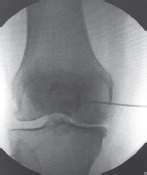

The objective aspect of the reduced pain syndrome severity after the administration of BMAC or PRP was the disappearance or significantly reduced size and decreased signal intensity in the area of previously identified bone marrow edema according to MRI (Fig. 5) [4].

Fig. 5. Decrease in signal intensity and the size of the bone marrow edema zone in the area of the femoral and tibial condyles after injection of BMAC: a — before injection; b — after 3 months